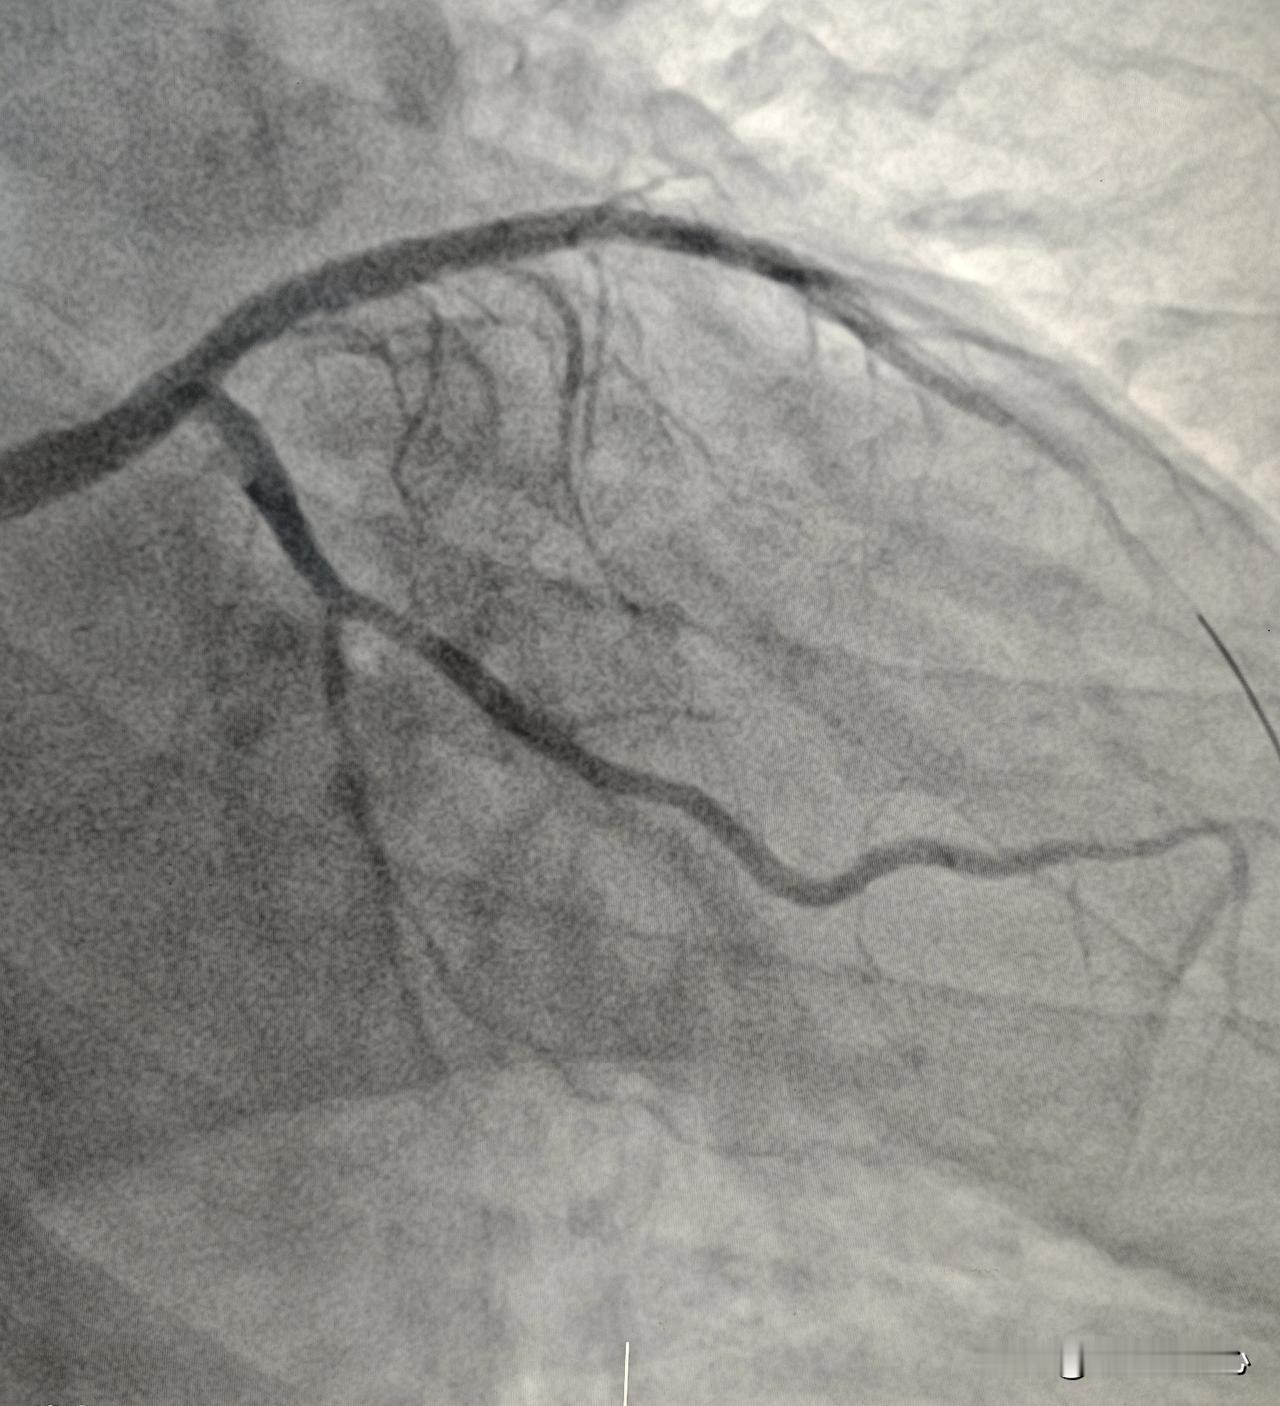

来看看 2018 年到 2025 年 7 年间冻龄不衰老的冠状动脉。 66 岁男性,7 年前因为冠心病右冠做了心脏支架,前降支狭窄 70% 左右没有做支架。期间一直规范化吃药治疗,烟是一根都没抽了。今年来医院复查造影,右冠支架通畅,前降支原有血管也没有加重。 血管衰老跟人衰老一样,随着年龄增长和外界不良因素的影响,一般呈现逐渐缓慢加重的趋势。而这位患者 7 年间前降支一点都没有加重,血管衰老好像在他身上停滞了。动脉硬化冠心病治疗药物非常重要,比做支架更重要。